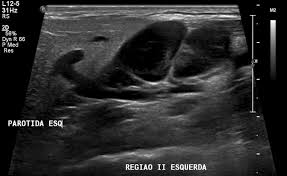

Cureus Evaluation Of B Mode And Color Doppler Ultrasound In The Diagnosis Of Malignant Cervical Lymphadenopathy

Cureus Evaluation Of B Mode And Color Doppler Ultrasound In The Diagnosis Of Malignant Cervical Lymphadenopathy from assets.cureus.com

An ultrasound may be used to check for certain cancers in various different ways. What an ultrasound can detect? 31 533 просмотра • 28 сент. Cysts or abnormal growths in the liver, spleen, or pancreas. Brook's personal experiences as a patient with throat they are also used to detect cancer and follow up its progression and response to therapy. Some genetic disorders, such as fanconi anemia, can increase the risk of developing precancerous lesions and cancers early in life (30). Sometimes the cancer cells can spread into the nearby lymph nodes. Ultrasound can detect abnormalities indicating cancer in breast, liver, etc., but a definite diagnosis requires further tests like ct or mri scan. However, ultrasound does not produce images with the same level of clarity or detail as a ct or mri scan, nor can it confirm a cancer diagnosis on its own. A scanner then detects this substance to produce images. Ultrasound image of a neck mass. For head and neck cancers, immunotherapy medications may act on a specific protein in immune. An ultrasound of the neck uses high frequency sound waves to create a live image from inside of a patient's body.